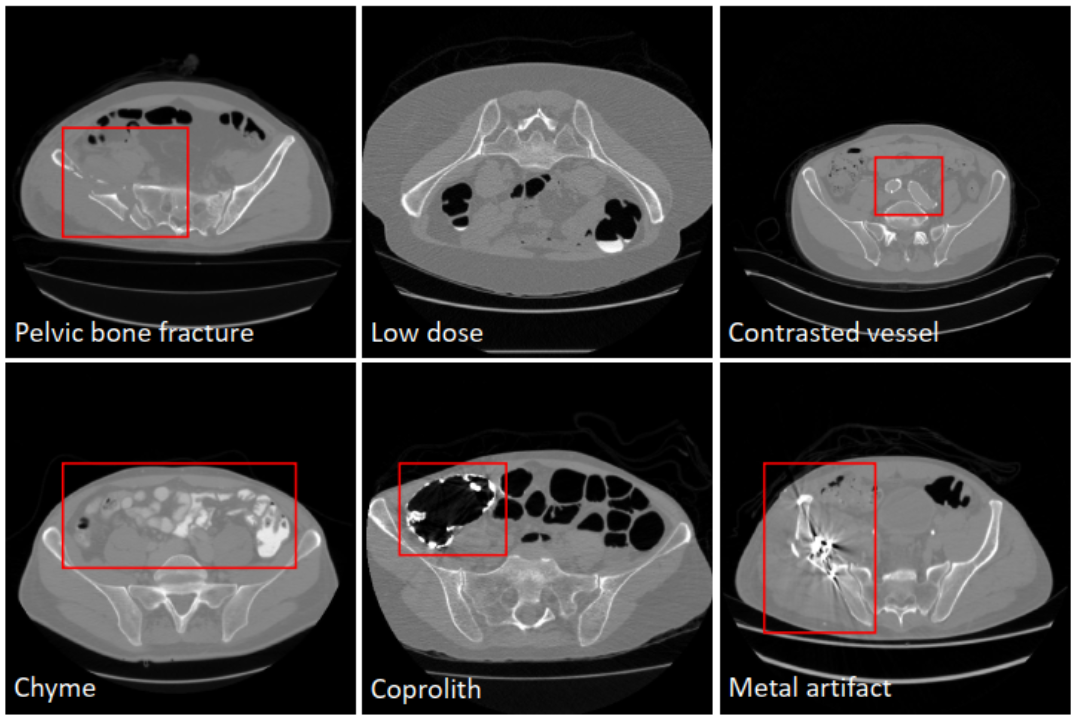

The first open source large-scale segmentation data set of pelvic anatomy, including 1184 3D CT pelvic data, segmentation labels, and baseline models. Cooperative unit: Jishuitan Hospital.